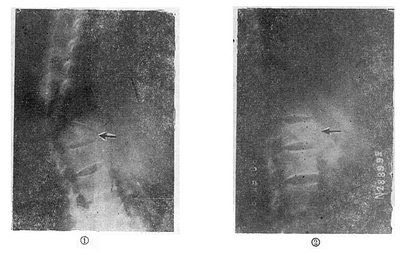

图73-15 椎体后部Chance骨折的治疗 (五)切片状骨折的治疗 因为这种骨折伴有整个韧带的完全撕裂,且常合并截瘫,用Harrington撑开棍治疗后方间隙反而会明显增宽。应选用强度较好的Luque或Dick装置为好,不仅能获得满意的复位(图73-16①~③),而且固定牢固,术后即可随意翻动病人,术后1-2即可让病人起床坐轮椅活动,有利于截瘫病人的康复与护理。

图73-16 切片骨折的治疗 (六)胸10以上的高位胸椎骨折截瘫 由于病人腰部的肌肉完全麻痹,会发生麻痹性侧弯和后凸畸形,用Harrington或Luque技术治疗,均不能解决腰椎固定到骨盆上的问题,所以都不能维持病人坐姿。由于腰骶部过度屈伸活动,很容易引起断棍、脱钩或钢丝的疲劳断裂(图73-17)。目前Galveston手术是解决这种骨折的最有效的方法。手术时作胸3~骶2正中切口,骨膜下剥离T3-4至S1-2、及髂后上嵴及髂骨外板,如Luque方法在T3-4至L5,每个椎板下穿过Luque钢丝。然后将事先弯好生理性胸后凸与腰前凸的两根金属棍,用Luque钢丝从胸3~4一直固定到髂骨坐骨切迹上方内外骨板之间。不仅牢固固定了骨折,而且能有效维持病人的坐姿(图73-18①②)。